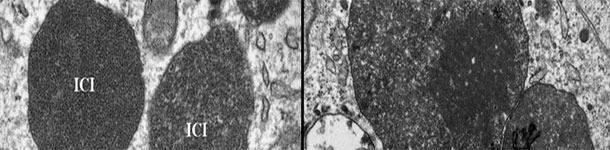

Microscopía electrónica de um gânglio linfático de um porco com PCV2-SD. Note-se a presença de corpos de inclusão intracitoplasmáticos de PCV2 (ICI); em algumas zonas, as partículas virais podem estar dispostas em estruturas paracristalinas (quadrado da imagem direita). Foto cortesia de Carolina Rodríguez-Cariño, tese de doutoramento.